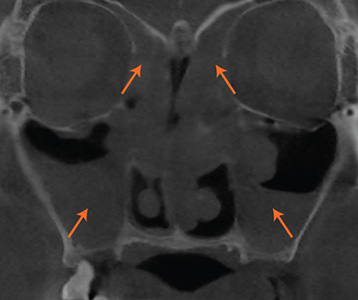

CT, 문진, 내시경, 후각, 음향,

통기도 검사 진행.

현재 상태를 정확히 분석합니다.